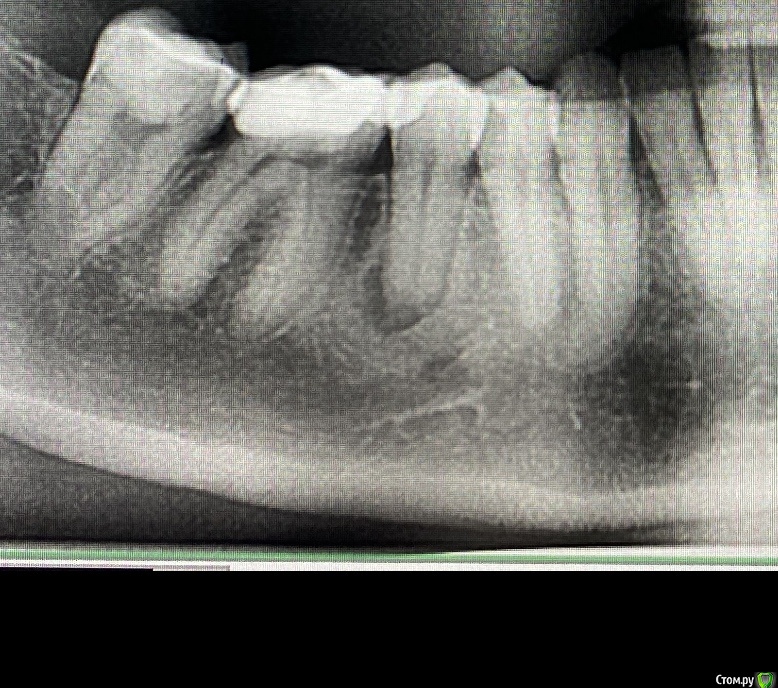

risus Опубликовано 30 ноября, 2020 Автор Поделиться Опубликовано 30 ноября, 2020 (изменено) Прошу извинить, снимок сделан до начала лечения, месяц назад. http://forum.stom.ru/topic/20613-sovety-patcientam-obiazatelno-k-prochteniiu/ Изменено 30 ноября, 2020 пользователем risus Ссылка на комментарий

risus Опубликовано 30 ноября, 2020 Поделиться Опубликовано 30 ноября, 2020 Здравствуйте! Могли бы вы посоветовать, что делать в данной ситуации. Три с года назад, я носила брекеты, когда в очередной раз дугу подтянули у меня дико разболелись зубы с правой стороны на нижней челюсти, в области 6 и 5. Я отправилась к ортодонту и доктор высвободил 6 зуб из дуги. Стало значительно полегче, но появилась странная чувствительность. Реакция на холодное вызывала в районе 6-5-4 зуба сильную, долгую, выкручивающую боль, что наводило на мысль о пульпите. Отправилась к терапевту. Сделали снимок, доктор сказал, что у 6 и 5 кариес под пломбой. Произвел лечение, депульпировать зубы не пришлось, пульпита по словам врача, не было. И к счастью, после лечения болевые ощущения прошли. Прошло три года. Делали КТ по поводу другого зуба, но на общем снимке, доктор заметила, что у меня гранулема на том самом 5 зубе, который лечили вместе с 6-м. Начали спасать 5-й зуб, как оказалось, нерв в нем уже умер. Острых болевых ощущений не было, к слову. Прочистили каналы, заложили лекарство, ничего не беспокоило. Через неделю убрали лекарство, положили кальций, и все было нормально, до тех пор, пока мне не отполировали пломбу на 7-м зубе. 7-у лечили давно, сбоку пломба была неровной и там часто собирались остатки пищи. Полировали пломбу недолго, но от холодного воздуха (или воды который исходил от слюноотсоса или бор машины) у меня появилась сильнейшая боль, точь в точь как 3 года назад после подтяжки дуги, только теперь она распространилась аж на 3 и 2 зубы. То есть, 6, 5, 4, 3, 2 – всю эту область зубов было больно, помогло обезболивающее. Сейчас некоторая повышенная чувствительность осталась на 3 и 2 зубе, а вот сильные болевые ощущения появляются в районе 6-5-4 зуба. Таким образом:4 зуб недавно пролечен – был глубокий кариес. После лечения не беспокоил. В 5 зубе все еще кальций и временная пломба, т.к нерва нет, болеть вроде не должен, но под ним гранулема, контрольный снимок будет сделан перед установкой пломбы.6 зуб на основании вышеописанных жалоб, перелечили, поставили новую пломбу. Доктор сказала, что визуально пульпита нет, но если будет болеть, то придется удалять нерв. Но, к сожалению, болит. Боль такая странная, жгучая и выкручивающая, усиливается при движении челюсти. Иногда сама проходит, особенно если не разговаривать, и побыть в покое, за ночь тоже успокаивается. И при этом, боль значительно усиливается, когда надавливаю не на зуб, а на десно в районе 6-5 зуба со стороны языка, хотя визуально десно не красное, не отекшее. Заложила метрогил-дента и на пол дня как рукой сняло, ничего не болело, никакой чувствительности, а сейчас не помогает. Завтра иду к врачу, боюсь, если депульпировать и 6 зуб, то это может не помочь. Потому что боль как бы не исходит из него, а просто ощущается вокруг 6-5-4. Может ли это быть проблемой, связанной с десной? Может ли это быть связано с гранулемой? И можно ли как-то точно проверить, воспален ли нерв, и нужно ли его удалять? В связи с тем, что болевые ощущения сейчас идентичны с тем, что было три года назад, можно ли говорить о хроническом пульпите? Ссылка на комментарий